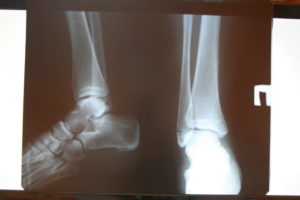

Диагноз перелома лодыжки ставится из совокупности данных опроса, осмотра и диагностики.

Для определения наличия перелома и его характера необходимо провести диагностические исследования, первым из которых является рентгеноскопия. Рентгеновский снимок выполняют в двух проекциях: боковой и передне-задней.

Дополнительными методами исследования сустава является сонография (ультразвуковое исследование), артрография и артроскопия.